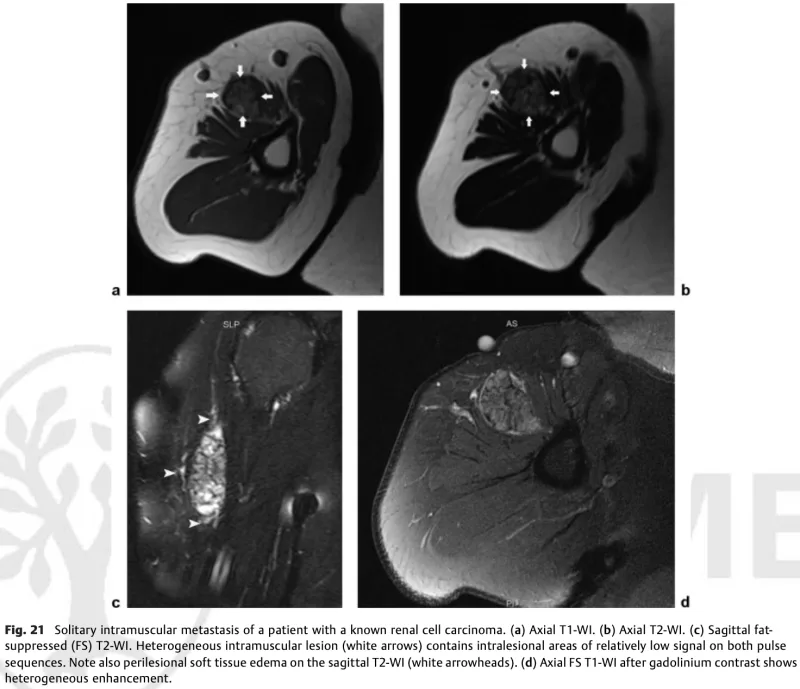

腎癌筋肉内転移

T1強調像8a0では, 筋肉より少し白っぽく, T2強調像(b)では白く, 脂肪抑制下T2強調像では, 白黒混合の不均一な像を示します.

引用元:Vanhoenacker FM. Soft tissue tumors about the shoulder.Semin Musculoskelet Radiol 2015. 19.

昨日受診した, 腎癌筋肉内転移が疑われる患者さんの造影MRIを確認.

やはり転移が疑われましたが, 良性の血管性腫瘍など, 他の病変も疑われます.

生検を行うか, 摘出術を行って病理検査を行うかですが, 腎癌は血流が豊富なので, 生検で針を刺すと出血して, 腫瘍を拡げてしまう危険性があります.

一方, 摘出手術では, 正常な筋肉も一部切り取る必要があり, また, 筋肉の表面と深部を通る神経(腋窩神経)を傷つける危険性があります.

患者さんは, 現時点で肺に転移があり, 経過を観察されているので, 泌尿器科のドクターに余命見込み等を照会して, その結果を診て検査方針を立てることにしました.